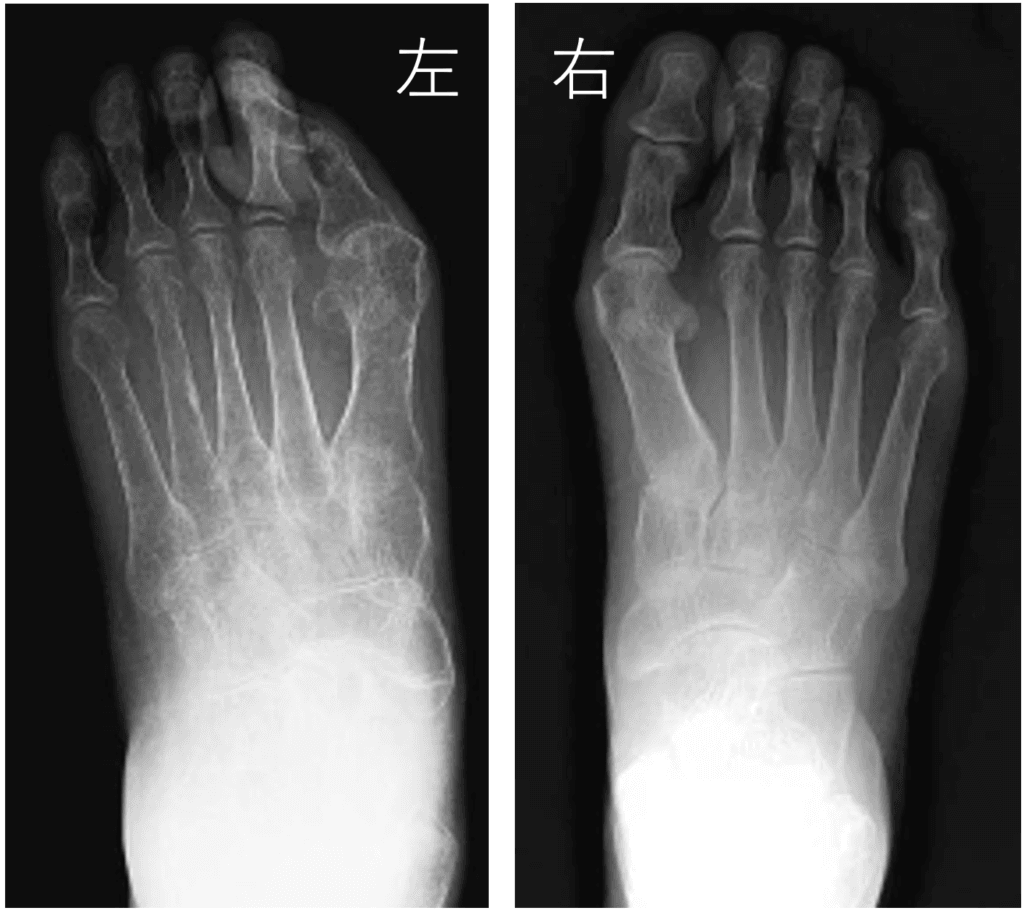

レントゲン上は、折れてしまった骨は骨癒合しています。

レントゲンを撮影すると、白く映る骨が薄っすら映ります。このことを「骨萎縮」と言います。

症状の緩和とともに「骨萎縮」も改善してきます。